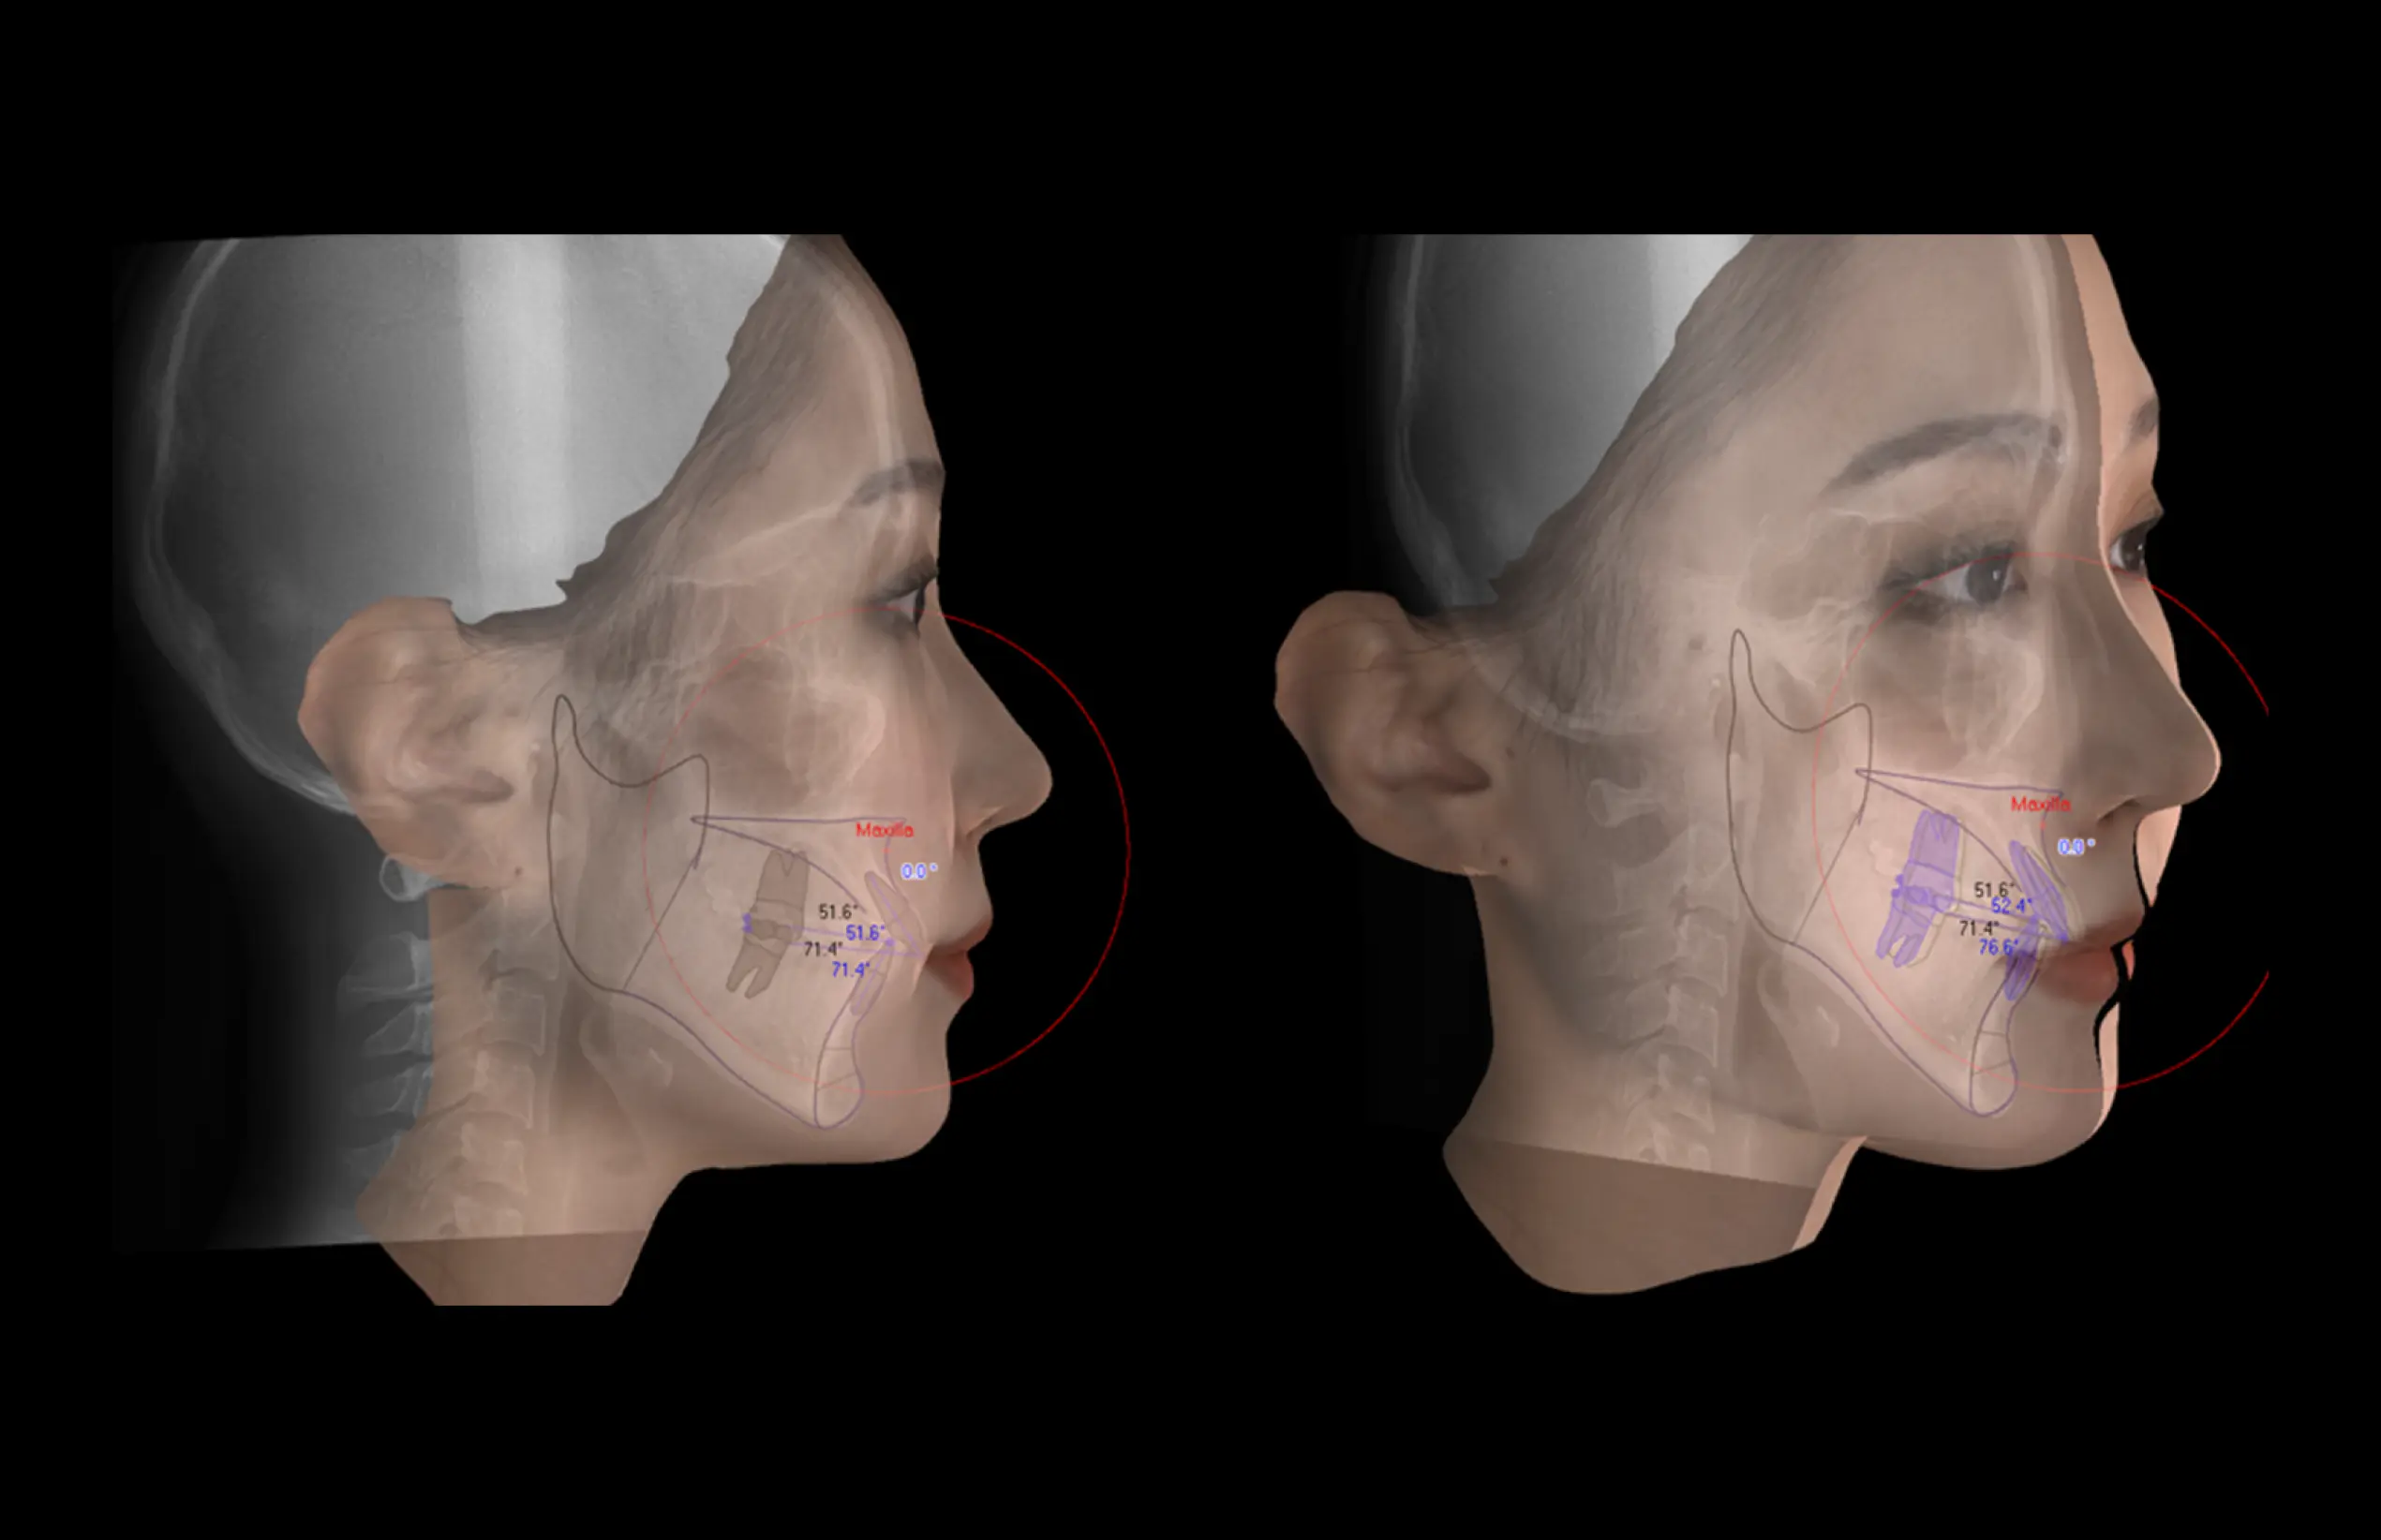

MDSDental Solution

더보기 오토 트레이싱

·환자의 X-ray (측면 & 정면)에서의 디지털

트레이싱

·클릭 한번으로 빠르고 정확한 AI기반의 자동

트레이싱